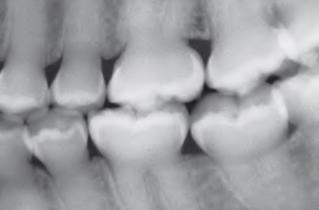

Buccal Bifurcation Cyst | 36, 46 Buccal (兩側 1/3) | 5-13y | - |

![]() |